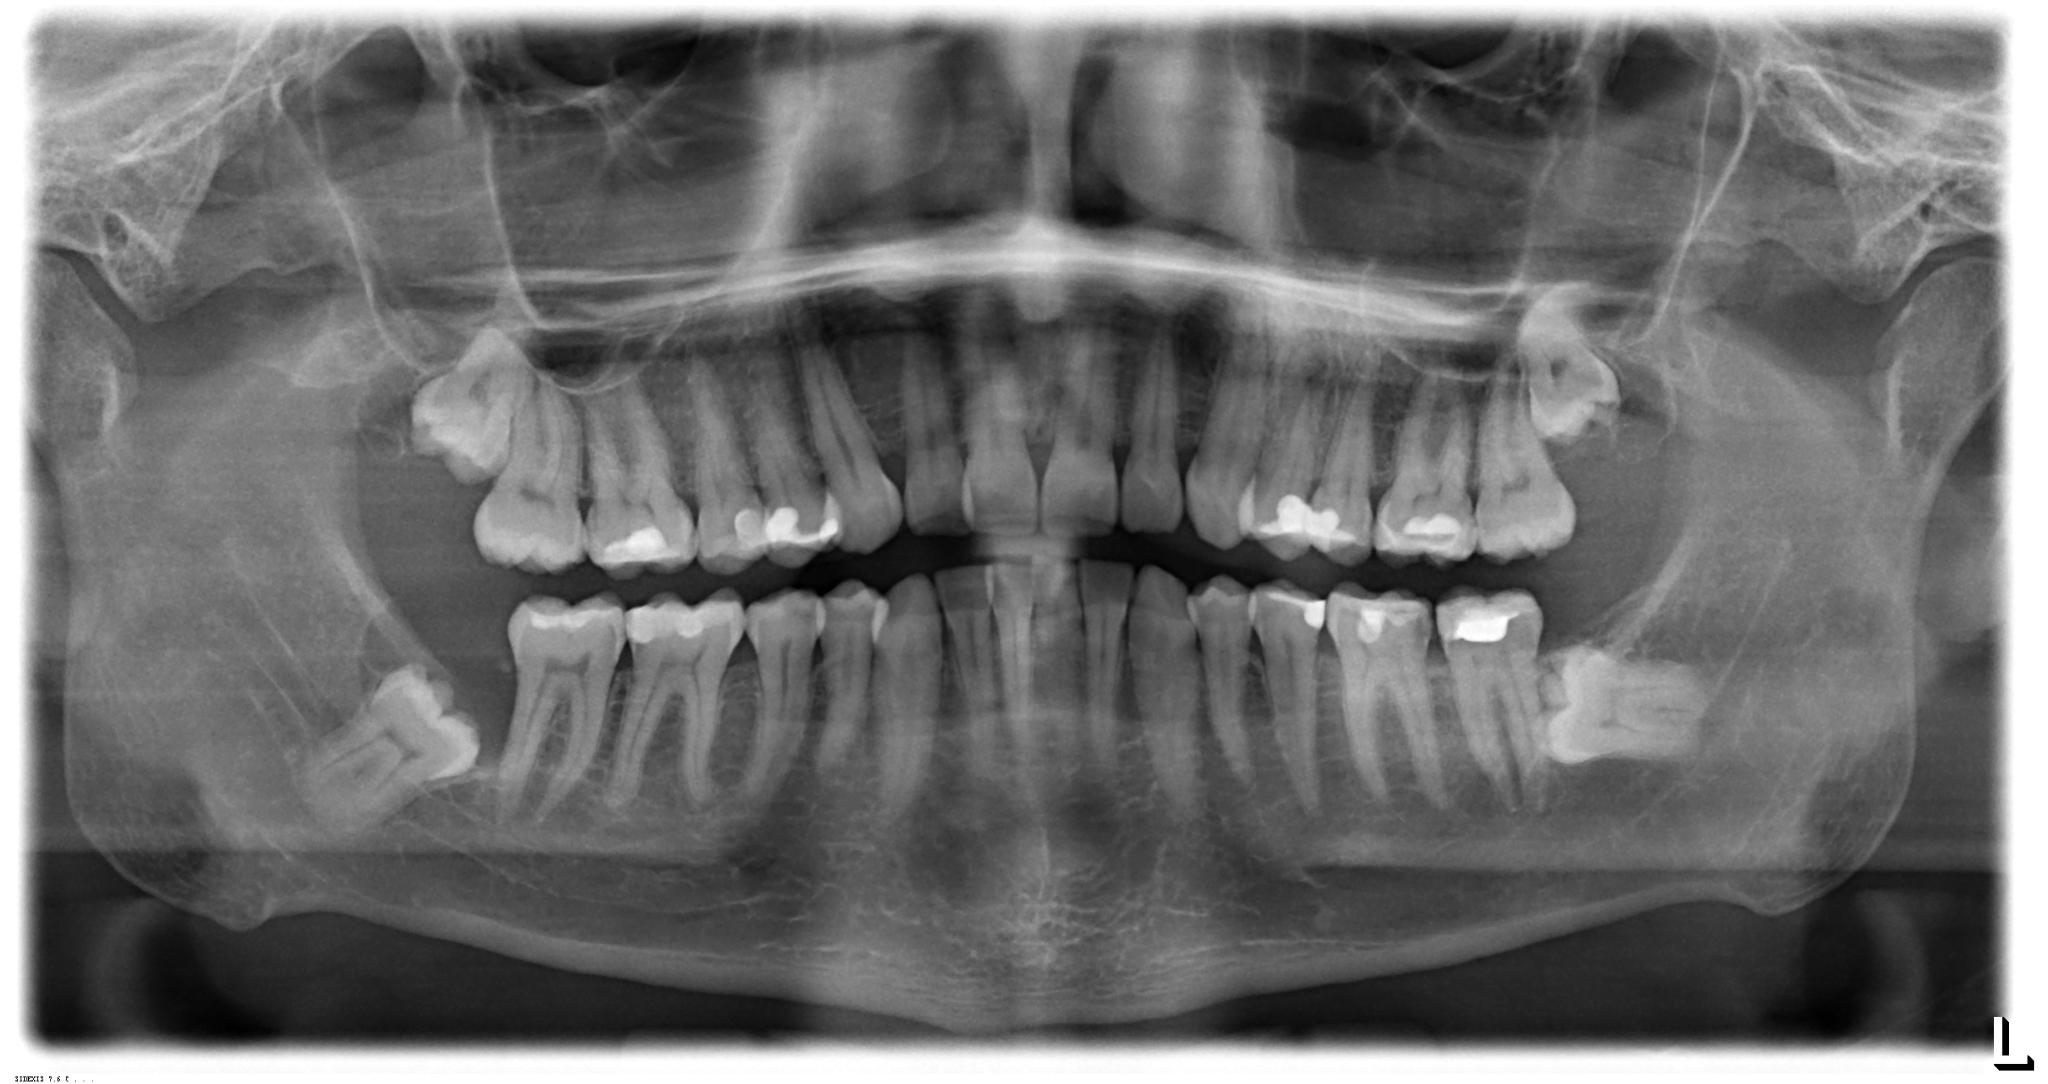

Bei vielen Menschen ist eine Entfernung der Weisheitszähne sehr sinnvoll. Doch erst nach dem Eingriff beginnt für viele Patienten die richtige Herausforderung: die Heilungsphase. Nun entscheidet sich, ob sich die Wunde schließt oder es in der Folgezeit zu Komplikationen wie etwa Entzündungen, Schwellungen oder Nachblutungen kommt. Insbesondere die richtige Pflege und eine gute Ernährung sind wichtige Bausteine für eine gesunde Verheilung. Ihre Oralchirurgen aus Düsseldorf geben hilfreiche Tipps, wie Sie die Wunde in den Tagen nach der Weisheitszahnentfernung optimal versorgen, was Sie bei der Mundhygiene beachten sollten und welche Lebensmittel gut geeignet sind.